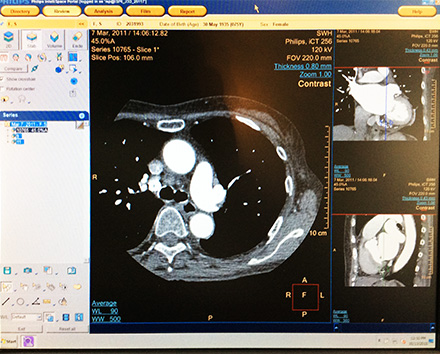

CT、MRI撮影を行い、造形物の基となるデータを収集します。

撮影された画像を再構成し、3D表示します。